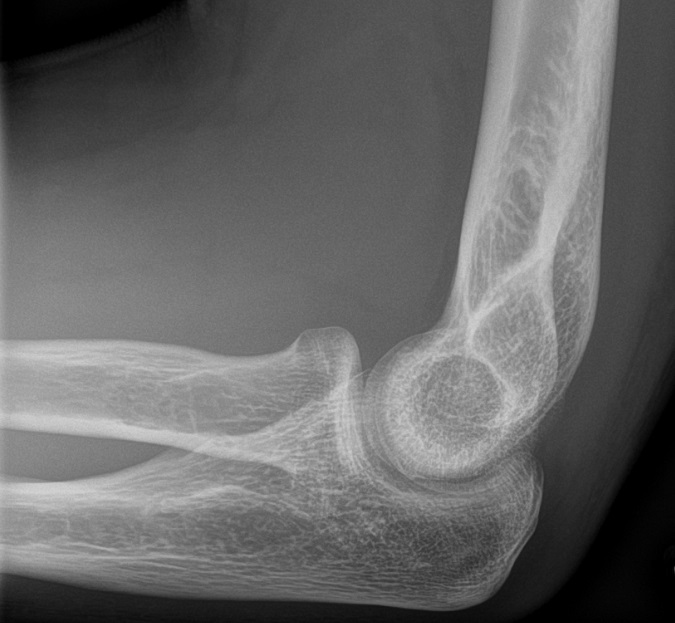

Normal sidobild (vuxet skelett)